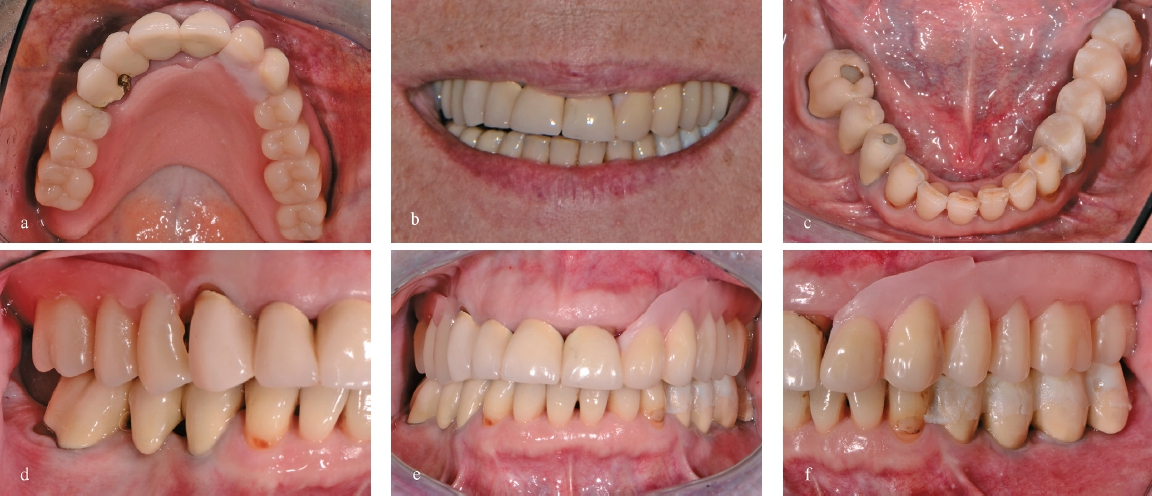

Definitive Versorgung im Unterkiefer

Sechs Monate nach Fertigstellung der Oberkieferhybridprothese folgte die definitive Versorgung im Unterkiefer. Die verblockten und nicht passgenauen Kronen 34-35i-36i wurden entfernt und ein direktes Provisorium für den Zahn 34 angefertigt. Die beiden Implantate 35i und 36i wurden mit standardisierten Healing-Abutments provisorisch versorgt. Nach chirurgischer Weichteilkorrektur und Nachpräparation des Pfeilerzahnes 34 wurde die Situation abgeformt und mit neuen einzelnen VMK-Kronen und -Implantatkronen versorgt (Abb. 20 u. 21).